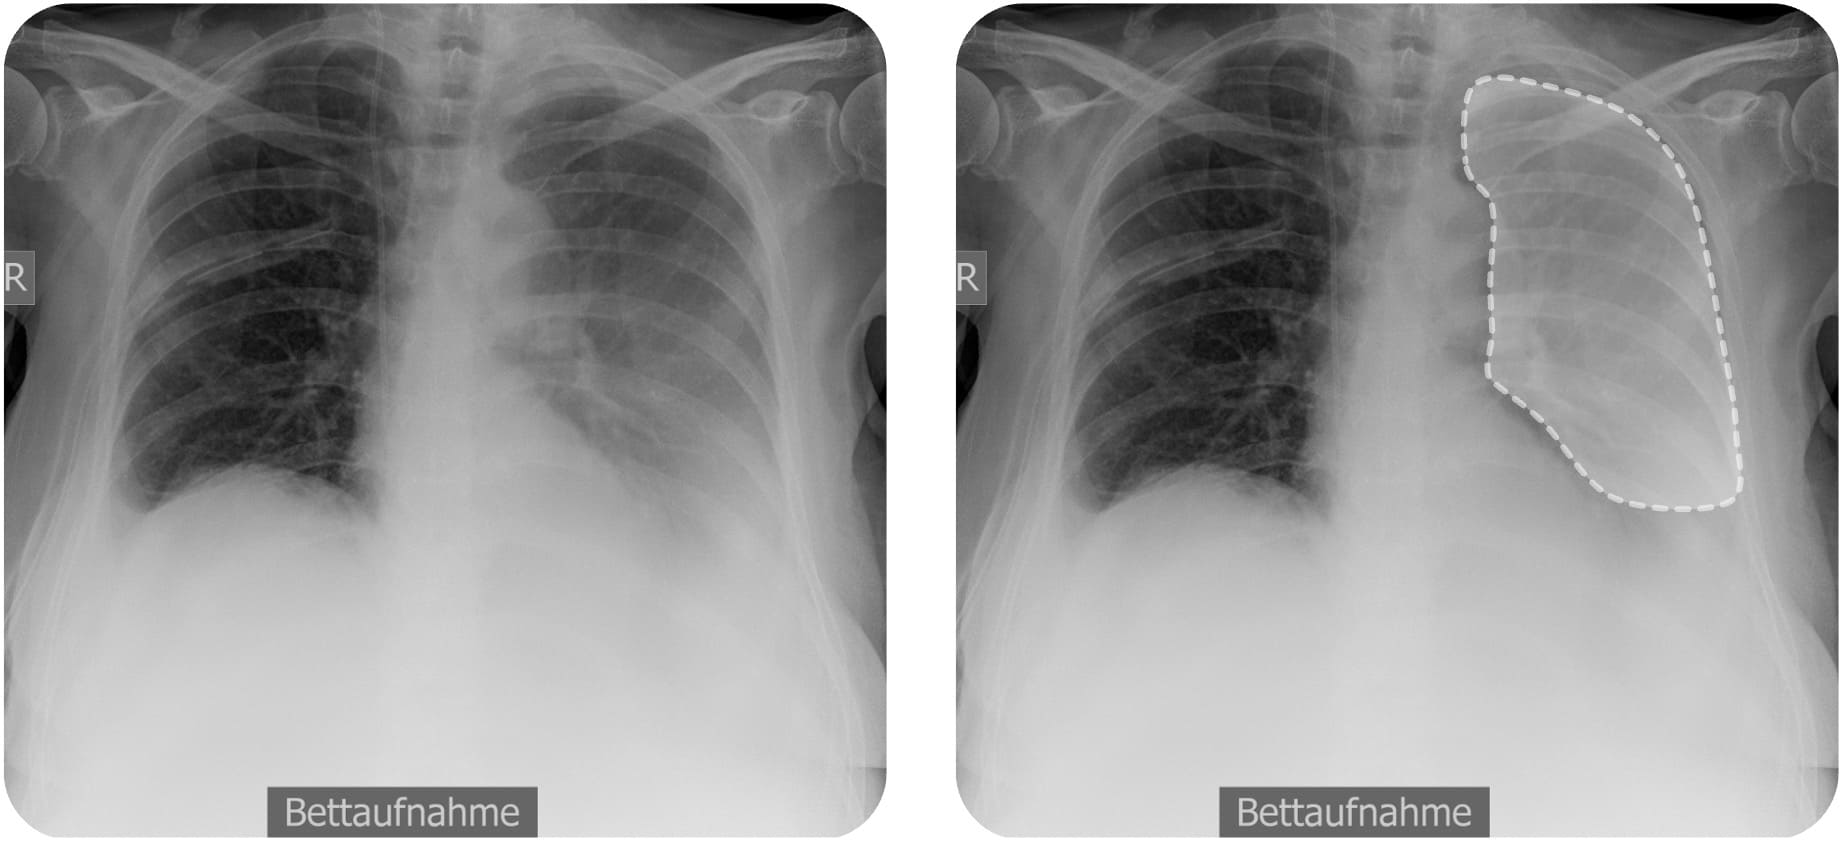

Radiologische Zeichen in der Liegendaufnahme

Im Liegen ist ein Pleuraerguss

Hellerhoff, CC BY-SA 3.0, https://creativecommons.org/licenses/by-sa/3.0, via Wikimedia Commons. Die Abbildung ist ein Derivat der oben genannten Abbildung. Das Bild wurde zugeschnitten. Es wurde das Overlays ergänzt.

Eine besondere Herausforderung ist der Vergleich der Ergussmengen von Steh- und Liegendaufnahmen